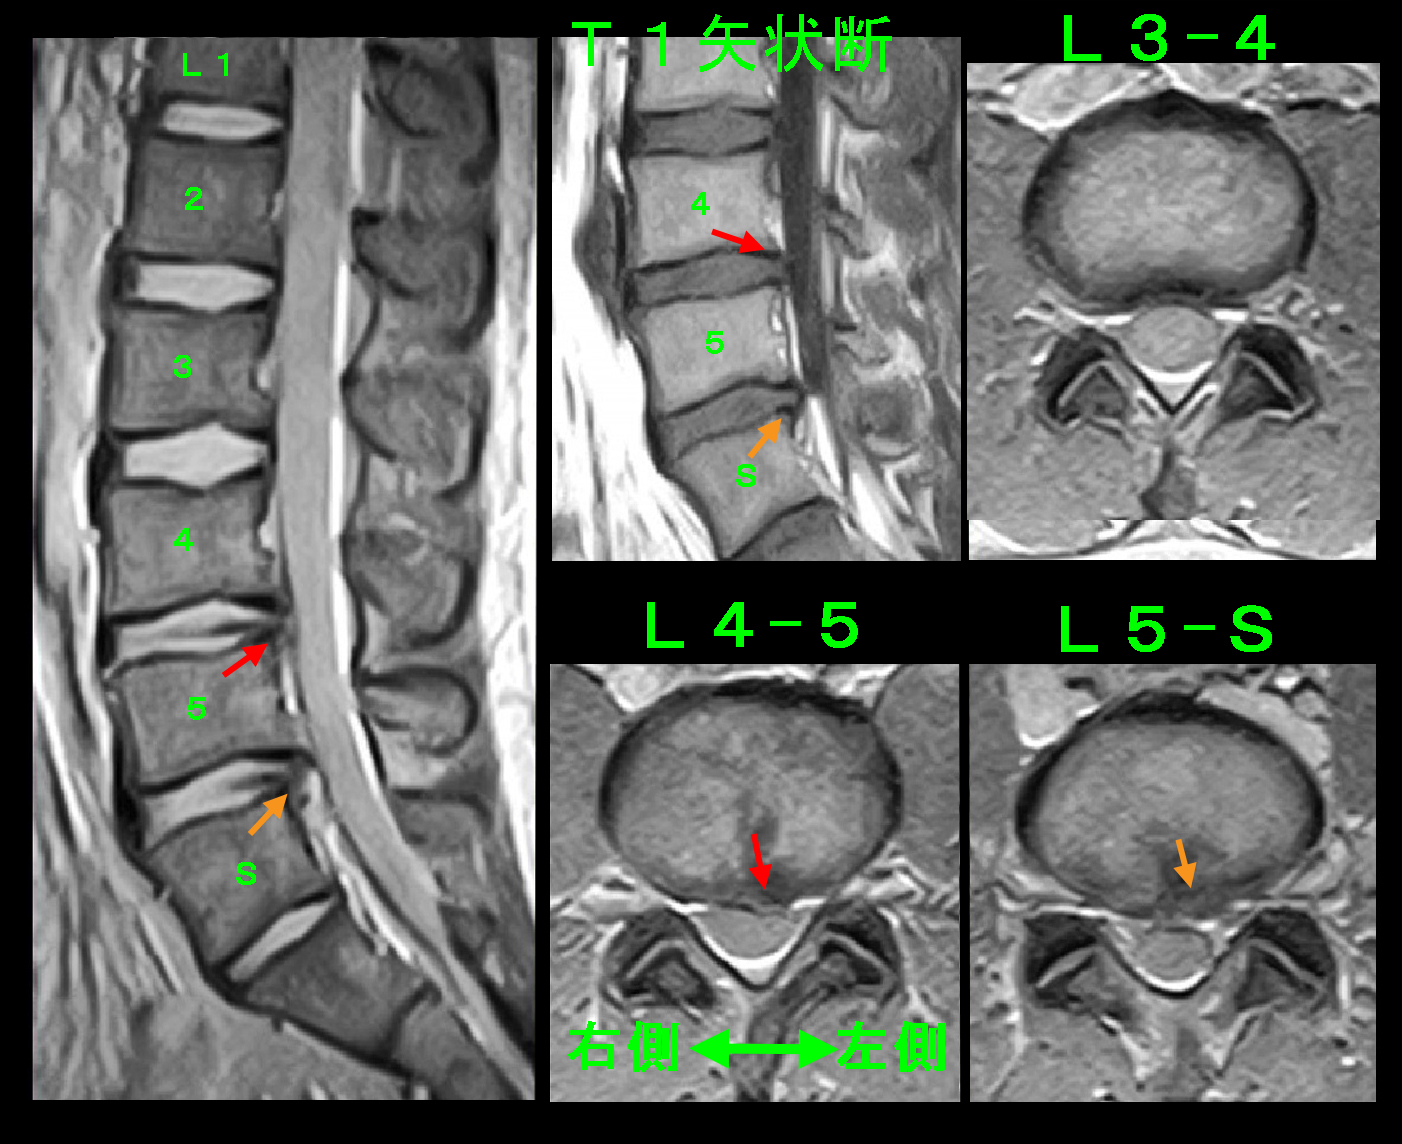

25才男 Xp1.jpg

腰痛に対する治療は一般的なレントゲン撮影後に鎮痛剤とシップで様子をみる治療と、MRI検査を行い、検査結果によっては積極的に神経根ブロックを行うという2つの治療方針を提示していますが、患者さんは後者の方針を希望されました。